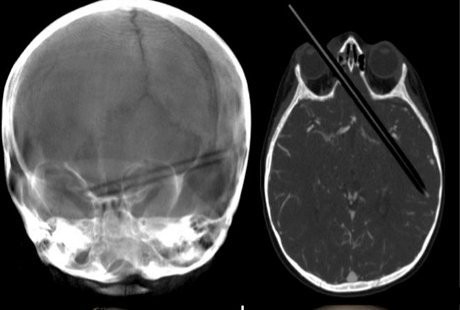

Bruk! Jatuh dari Kursi, Bocah Ini Tertusuk Pensil di Matanya - detikHealth Selasa, 29 Jan 2013 14:11 WIB Foto: Fox News Jakarta - (vit/vit) Infografis Lainnya Infografis Feeding Difficulty Vs Picky Eating, Apa Beda & Dampaknya bagi BB Anak? Infografis Waspadai Dampak Picky Eating pada Anak, Berikut Cara Jitu Cegahnya Infografis Infografis: Strategi dan Formasi Ideal untuk Menang Lomba Balap Bakiak